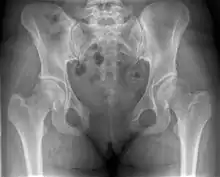

| Post traumatic diastasis of symphysis pubis | |

An X-ray film will show a marked gap between the pubic bones, normally there is a 4–5 mm gap but in pregnancy, hormonal influences cause relaxation of the connecting ligaments and the bones separate up to 9 mm. To demonstrate instability of the joint the patient is required to stand in the "flamingo" position, (standing with weight on one leg and the other bent).[2] A vertical displacement of more than 1 cm is an indicator of symphysis pubis instability.[3] A displacement of more than 2 cm usually indicates involvement of the sacroiliac joints.